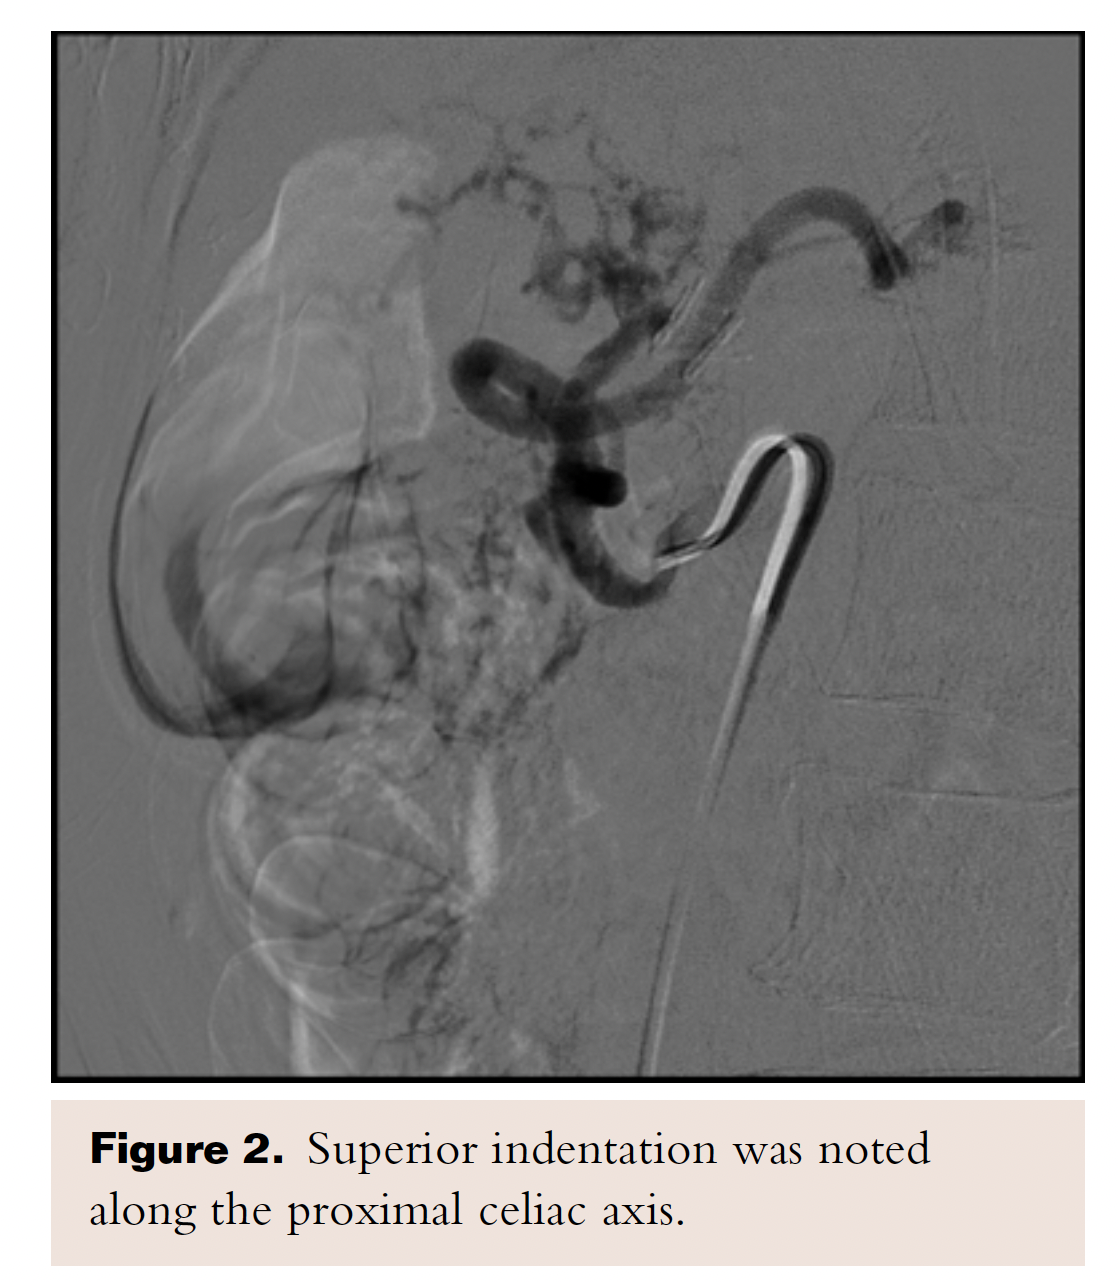

Given her age and co-morbid disease, the patient’s risk stratification was high for a moderate-to-high risk procedure; the patient was judged to be a poor surgical candidate and so the decision was made to refer her to interventional cardiology for consideration of less invasive treatment. A selective angiography of the celiac trunk was performed via the right common femoral artery with a 6 Fr system. During angiography, both inspiration and expiration films were compared; celiac artery stenosis was more prominent during expiration, and a characteristic superior indentation was noted along the proximal celiac axis (Figure 2), which led to the confirmation of MALS diagnosis. The celiac trunk was engaged with a 5 Fr, 0.035˝ Slip-cath VS 80 cm (Cook Medical), and the lesion was crossed with a 0.035˝ guidewire (Boston Scientific). Percutaneous transluminal angioplasty (PTA) of the proximal celiac trunk was performed with a 6.0 x 20 mm Mustang balloon (Boston Scientific). As expected, there was no significant angiographic improvement, so a 5.0 x 22 mm Cast stent (Atrium Medical Corporation) was deployed at 4 atm and postdilated at 10 atm. Final angiographic results showed reduced narrowing from 90% to 0%. IMA and SMA were patent (Figure 3).